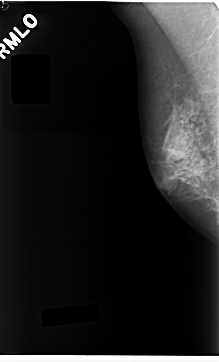

Digital Database for Screening Mammography

Volume: benign_01 Case: C-0237-1

C_0237_1.RIGHT_MLO

ics_version 1.0

filename C-0237-1

DATE_OF_STUDY 19 8 1994

PATIENT_AGE 62

FILM_TYPE REGULAR

DENSITY 3

DATE_DIGITIZED 28 4 1998

DIGITIZER LUMISYS LASER

RIGHT_MLO LINES 4704 PIXELS_PER_LINE 2840 BITS_PER_PIXEL 12 RESOLUTION 50 NON_OVERLAY